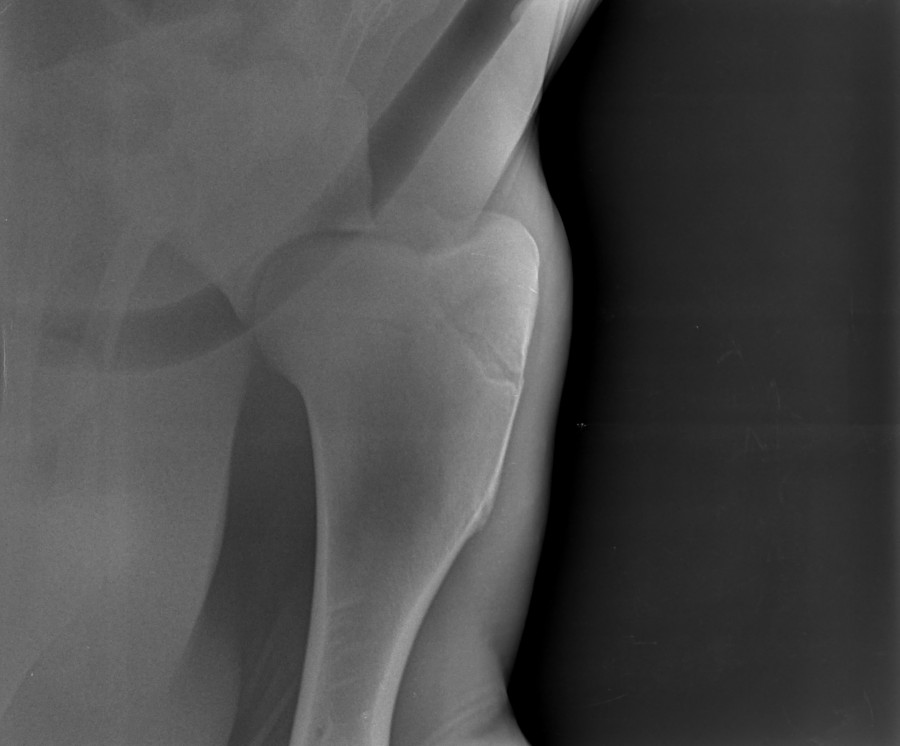

anokilie oui effectivement on a fait des radio. Non j'ai pas encore expliqué, si sur ma page uniquement.

Donc Voici les radios de granola, la première le 2mai, la deuxième le 23mai. D'après le veto la fracture se remet bien. On doit faire une radio dans 1mois. Donc il a le droit de sortir du box, même s'il trotte ou galope ce n'est pas grave mais faut éviter qu'il face le fou pour risquer de se refaire mal ou même de tomber.